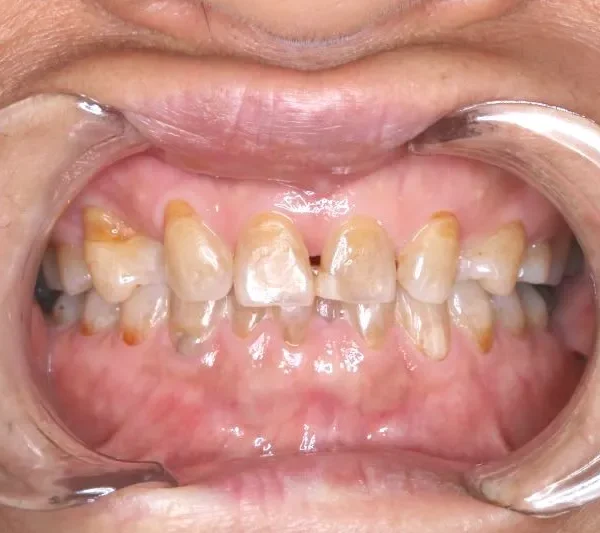

1.主訴 歯が足りない・ガタガタ

2.診断名あるいは主な症状 空隙歯列・先天性欠損歯

上の歯が2本足りないため上下のアーチが合わず、下の歯がガタガタになっています。

上下の幅をあわせ、噛み合わせから調整していきます。